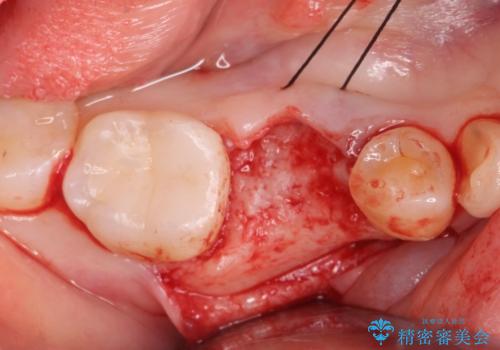

- 過去に抜けてしまった歯のところにインプラントを入れたいとの事で来院。

CTで確認したところ骨の高さや厚みがインプラント埋入できる状態でしたのでインプラント治療を行いました。